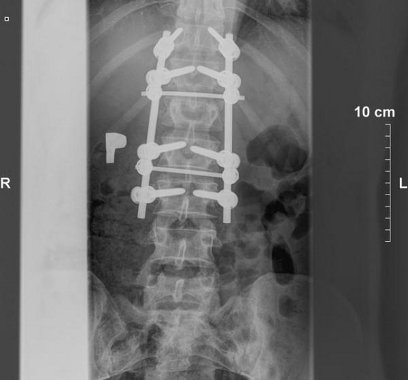

Do wykonywanych zabiegów w zakresie kręgosłupa należy zaliczyć też zabiegi resekcji trzonów i implantów trzonów kręgów w odcinku lędźwiowym kręgosłupa. Ponadto podejmuję się leczenia powikłań osteoporozy kręgosłupa. Moja oferta to również stabilizacja tylna, międzywyrostkowa w dyskopatii lędźwiowej i zespole po nukleotomii.

- stabilizacje transpedicularne i implanty międzytrzonowe PLIF Plivios ,

- stabilizacja kręgosłupa lędźwiowo-krzyżowo-biodrowa,

- stabilizacja złącza piersiowo-lędźwiowego,